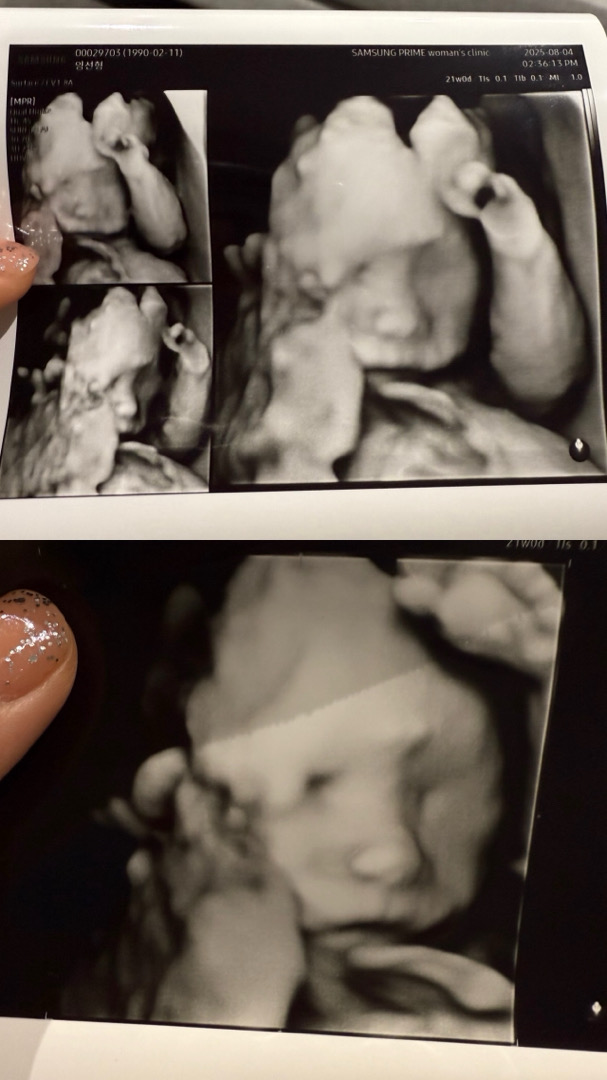

21주 2차 기형아검사갔다가 얼굴보고왔어용

검사결과 특별한 이슈없이 건강해서 넘 기뻤어요 운좋게 얼굴도 보고 왔는데 한달만에 보니 크기도 체중도 살도 올라와서 제법 아기같은 모습이라 뭉클했어요 🥹🩵🩵

430g이라고 하셨던거 같아요 😳😳🌸

어머 ㅎㅎㅎ 저흰 440g이요! 비슷하네요 ㅋㅋ 잘 자라고 있나봐요 😄